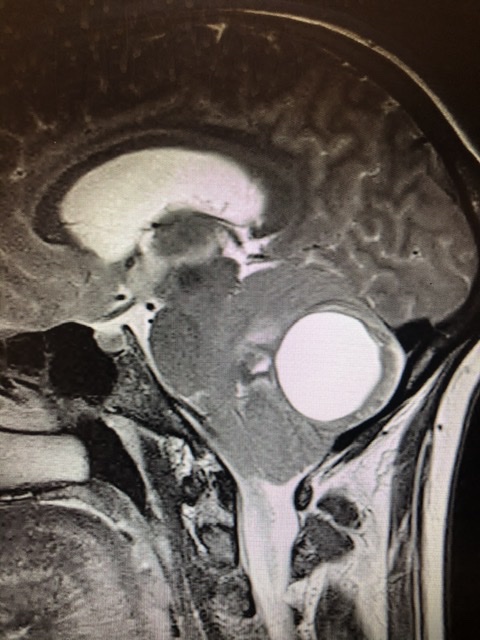

I posted this to the images thread but I’m not sure that actually gets seen now that it’s in the side bar (at least on the mobile website). I think this is a very important lesson for residents and fellows (and maybe a reminder for people stuck in the grind) that every so often we have a chance to really make a difference. Also, review the images yourself.

This patient came to me yesterday for severe neck pain and headaches, progressive for 6 months. She came in a wheelchair, could barely transfer to the exam table, crying out in pain and nearly vomiting. Had been to the ER the day before and they gave her a toradol shot and sent her home. She had an MRI c-spine a month ago. For some reason they had grabbed a T2 Sag view of the brain too, but the radiologist made no comment on the brain in the report - just some disc bulges and central and foraminal stenosis in the spine. Pulled up the brain images for a quick look given her complaint of dizziness. Exhibit A:

(I’ll give you a hint: there’s not normally a golf ball size cystic lesion in the middle of the cerebellum...)

Best I can figure, the rad tech must have noticed the lesion on the scout image, grabbed the T2 brain, but somehow this was not communicated to the radiologist.

I talked to the on call neurosurgeon and sent her to the ER. She was very ataxic but surprisingly mild disturbance of finger to nose, rapid alternating movement, or extraocular movement. Did complain of progressively worsening headaches, loss of balance, visual aura (like a kaliedascope around the edge of her vision), numbness of head and arms, and hearing loss. (Update: She’s in the OR now.)

The c spine set cut off just below the lesion. I suspect it was a failure of communication- an alert tech saw the lesion on the scout, grabbed a set of images of the brain, but just assumed the radiologist would look at them, or sent a message that then got lost. The radiologist, probably due to having a deeply set algorithm for how he reads images, breezed through the c spine and didn’t notice there was an extra set of images. There is no way he even glanced at it in passing. That lesion is impossible to miss.

There was no CT head. She had an MRI brain within 2 hours of her arrival at the hospital though. Cyst looked about the same size. There was some enhancement in a small area at the posterior aspect of the cyst.